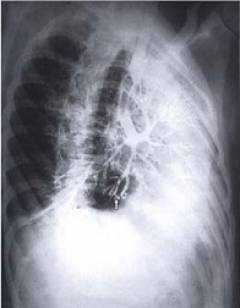

Бронхография - это рентгенологическое исследование трахеобронхиального дерева, осуществляемое вслед за введением в просвет трахеи и бронхов йодсодержащего рентгеноконтрастного вещества. После обволакивания им стенок бронхиального дерева возможна визуализация анатомических изменений. Фиб-рооптическим бронхоскопом контрастное вещество можно ввести в нужную часть легкого и получить ее снимок. В связи с развитием компьютерной томографии к бронхографии в настоящее время прибегают реже. Ее могут производить под местной анестезией с введением анестетика через катетер, подведенный через бронхоскоп; у детей и при необходимости выполнения бронхоскопии может потребоваться наркоз.

Бронхография - рентгенологическое исследование бронхиального дерева, которое проводится после введения в бронхи рентгенконтрастного вещества, изготовленного на основе йода. После того, как контраст обволакивает стенки бронхов изнутри, они становятся хорошо заметны на рентгеновских снимках.

Бронхография представляет собой исследование бронхиального древа, выполняется при помощи контрастного вещества. Оно вводится в просвет бронхов, после чего выполняется ряд рентгеновских снимков. На сегодняшний день это исследование уступает по информативности многим другим методам, поэтому используется достаточно редко. Однако в клиниках, где отсутствует новое оборудование, пациентам все еще назначают рентген бронхов.

Бронхография